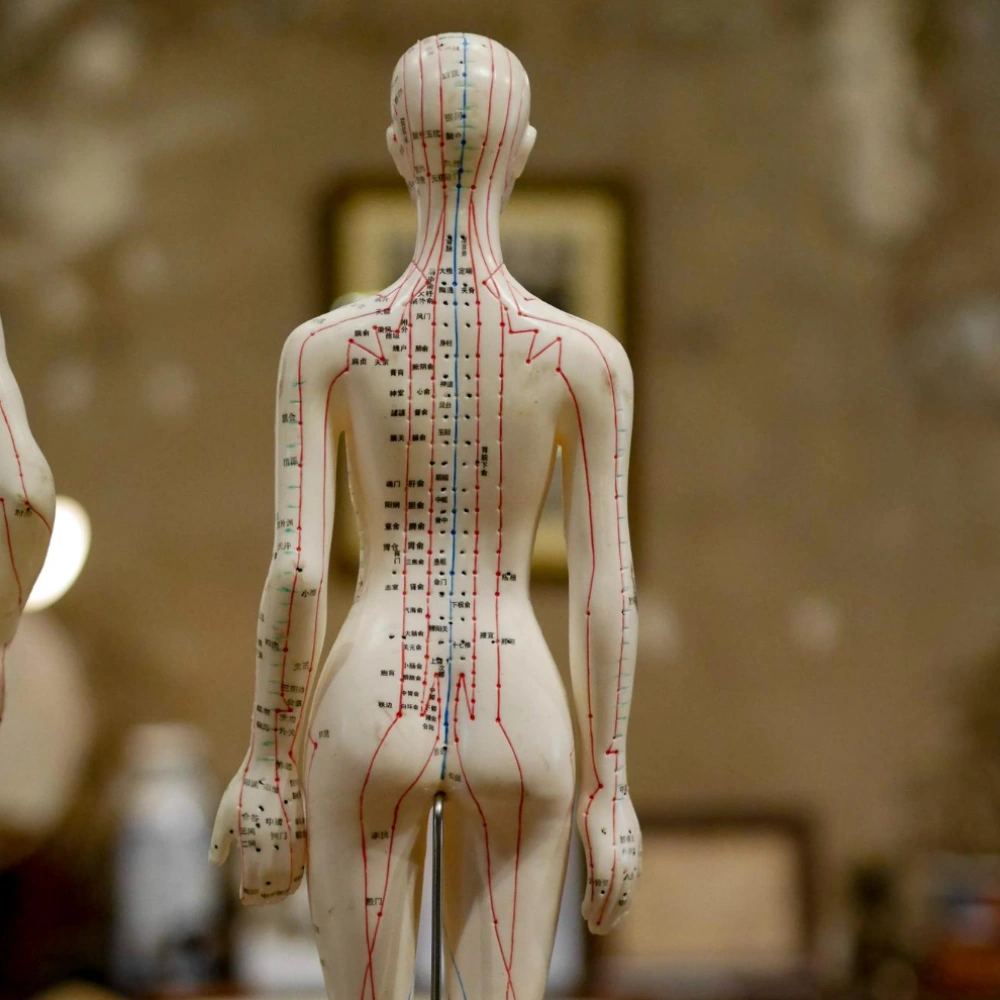

Qi przepływa przez określone ścieżki zwane meridianami. W ciele znajduje się czternaście głównych meridianów. Każdy z nich jest połączony z określonymi narządami i gruczołami.

Ścieżki południków są jak rzeki płynące wewnątrz ciała. Tam, gdzie płynie rzeka, transportuje życiodajną wodę, która zapewnia pożywienie ziemi, roślinom i ludziom.

Podobnie, tam gdzie przepływają ścieżki południków, dostarczają życiodajnej Qi, która zapewnia pożywienie każdej komórce, narządowi, gruczołowi, tkance i mięśniom w ciele.

Po wykryciu zaburzeń równowagi Qi, akupunkturzysta umieści cienkie, sterylne igły w określonych punktach akupunktury wzdłuż ścieżek południka. To bezpieczne i bezbolesne wprowadzenie igieł może odblokować niedrożność i zrównoważyć Qi tam, gdzie utraciła równowagę. Po wykonaniu tej czynności Qi może swobodnie krążyć po całym ciele, zapewniając odpowiednie pożywienie komórkom, narządom, gruczołom, tkankom i mięśniom. Może to wyeliminować ból i przywrócić równowagę i harmonię, a także zdolność organizmu do samouzdrawiania – ostatecznie prowadząc do optymalnego zdrowia i dobrego samopoczucia.